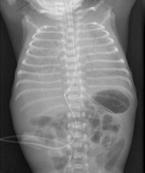

為一種的罕見的疾病,其特征為既往健康的孩子發(fā)生急性發(fā)作的嚴(yán)重休克,腦病和其他癥狀,并導(dǎo)致死亡或極其嚴(yán)重的神經(jīng)系統(tǒng)損害結(jié)果。發(fā)病迅速,死亡率高,生存者易留有嚴(yán)重的神經(jīng)后遺癥。其特點(diǎn)是突發(fā)的昏迷和抽搐、休克、BCD、水樣腹瀉、代謝性酸中毒、肝腎功能障礙。出血性休克和腦病綜合征(HSES)主要發(fā)生在3~8個(gè)月之間的嬰兒(平均年齡為5個(gè)月),但也有報(bào)道發(fā)生于15歲。

- 常見癥狀:驚厥、昏迷、休克、腹瀉、發(fā)燒、嘔吐、高熱、便血